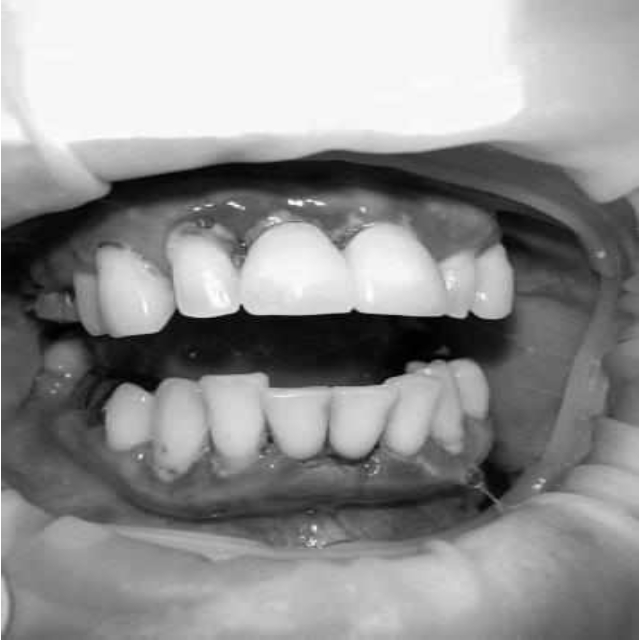

За пародонтологическим лечением обратилась женщина 61 года с жалобами на неприятный запах из полости рта, кровоточивость десен при чистке зубов, подвижность зубов, несостоятельность ортопедических конструкций.

Ранее у пародонтолога не наблюдалась. При осмотре выявлены: неудовлетворительная индивидуальная гигиена полости рта, пародонтальные карманы до 7 мм, обильная кровоточивость и гноетечение из пародонтальных карманов, подвижность зубов 4.2, 4.1, 3.1, 3.2 II степени, обильные над- и поддесневые зубные отложения (рис. 1). На ортопантомограме отмечается резорбция костной ткани до ½ длины корня, очаги остеопороза (рис. 2). Пациенту был поставлен диагноз хронический генерализованный пародонтит тяжелой степени тяжести. При осмотре была составлена пародонтограмма с использованием компьютерного зондирования (рис. 3).

Рис. 2. Ортопантомограмма исходной ситуации пациента состояния полости рта